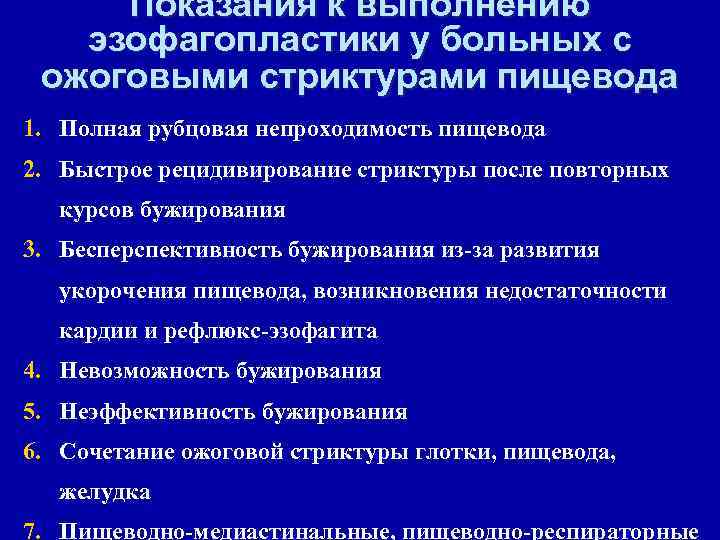

Показания к выполнению эзофагопластики у больных с ожоговыми стриктурами пищевода 1. Полная рубцовая непроходимость пищевода 2. Быстрое рецидивирование стриктуры после повторных курсов бужирования 3. Бесперспективность бужирования из-за развития укорочения пищевода, возникновения недостаточности кардии и рефлюкс-эзофагита 4. Невозможность бужирования 5. Неэффективность бужирования 6. Сочетание ожоговой стриктуры глотки, пищевода, желудка 7. Пищеводно-медиастинальные, пищеводно-респираторные